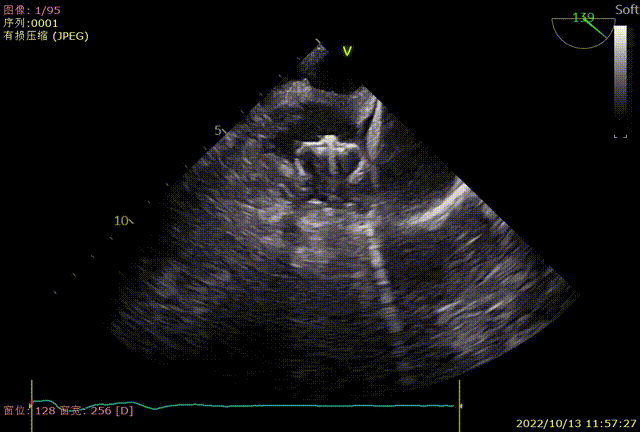

TEE0度封堵效果

TEE45度封堵效果

TEE90度封堵效果

TEE135度封堵效果